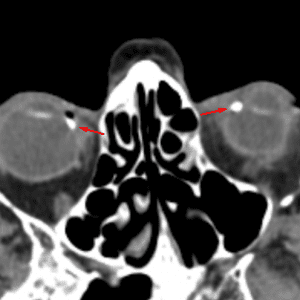

Optic Disc Drusen

Mimicking a foreign body or mass